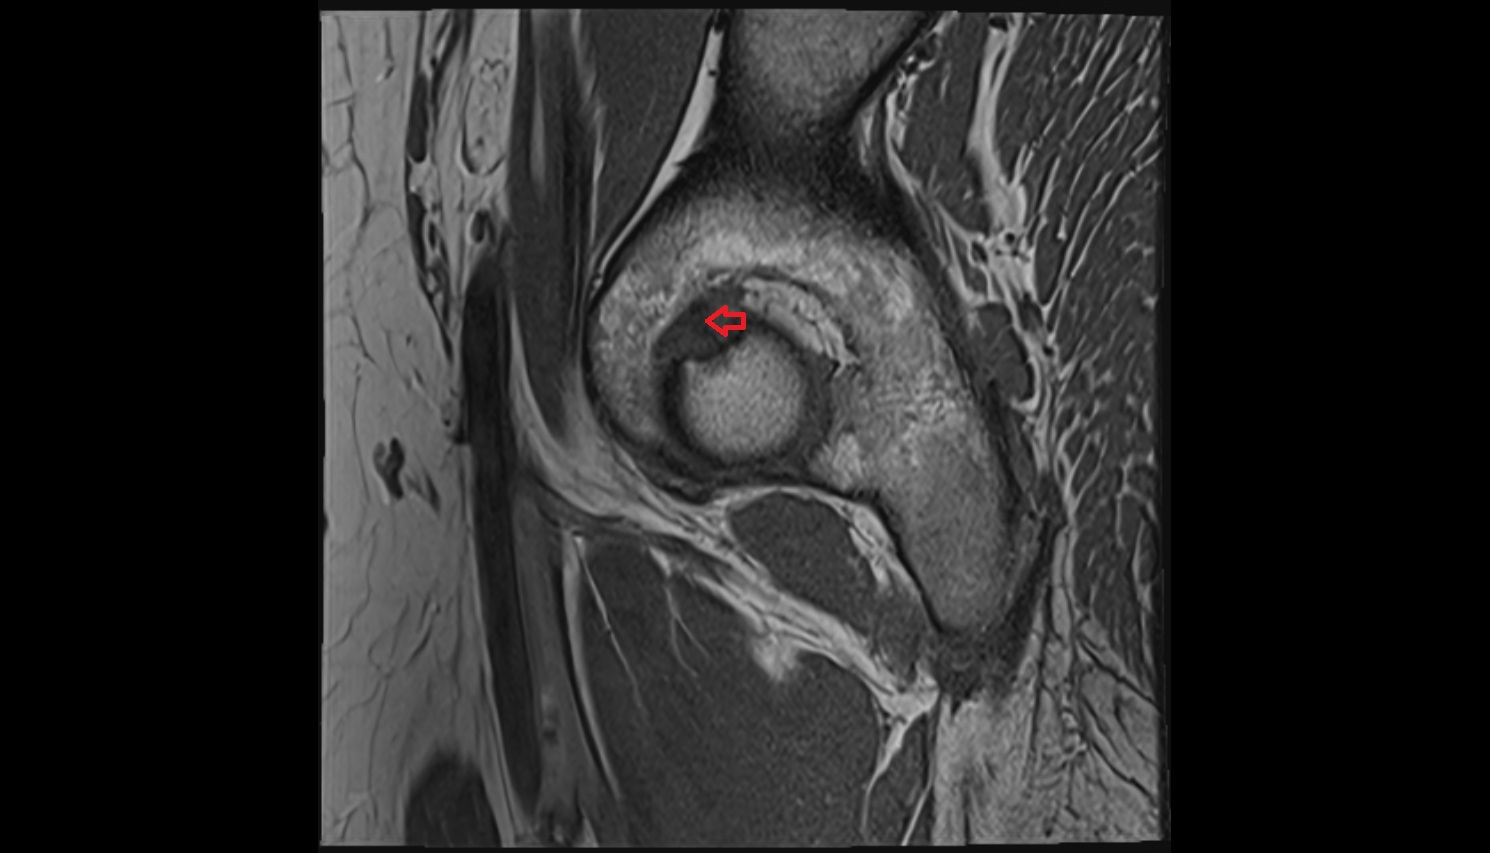

- Acetabular labrum

- Anterior cruciate ligament

- Posterior cruciate ligament

- Medial meniscus

- Lateral meniscus

- Knee Joint